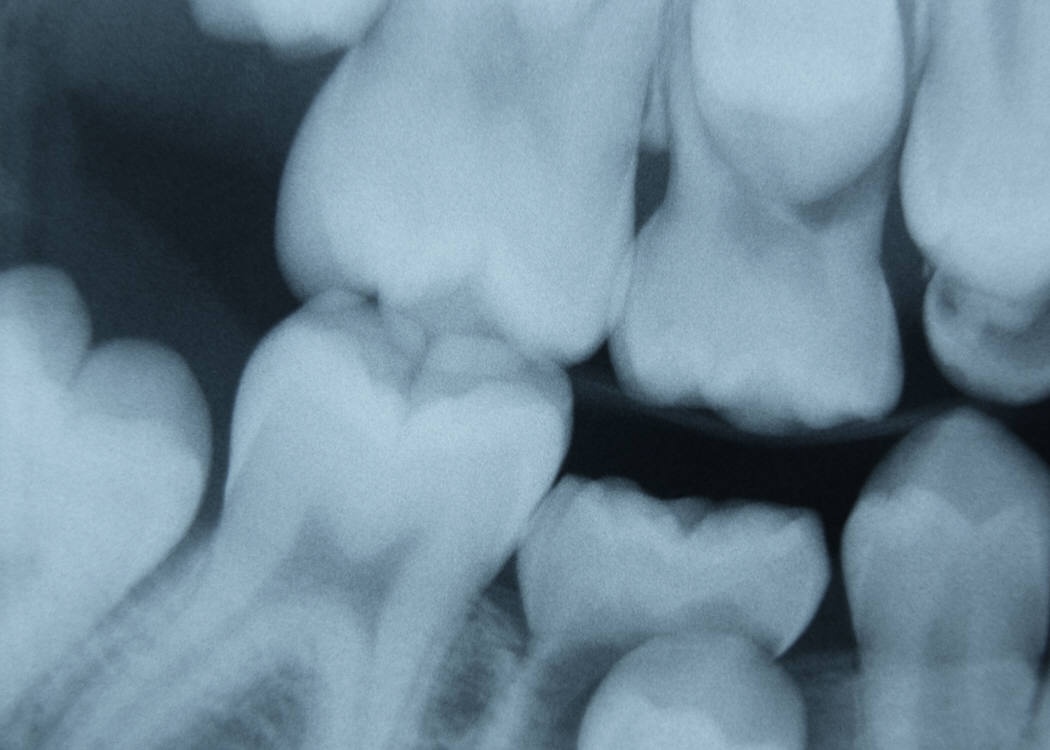

![]() |

| Bất thường về răng là một trong những lý do gây bệnh. |

- Bất thường về răng: mất răng làm giảm hiệu suất nhai, các răng lân cận bị xô lệch, bị hàn răng hoặc làm răng giả sai kỹ thuật, răng khôn mọc lệch...